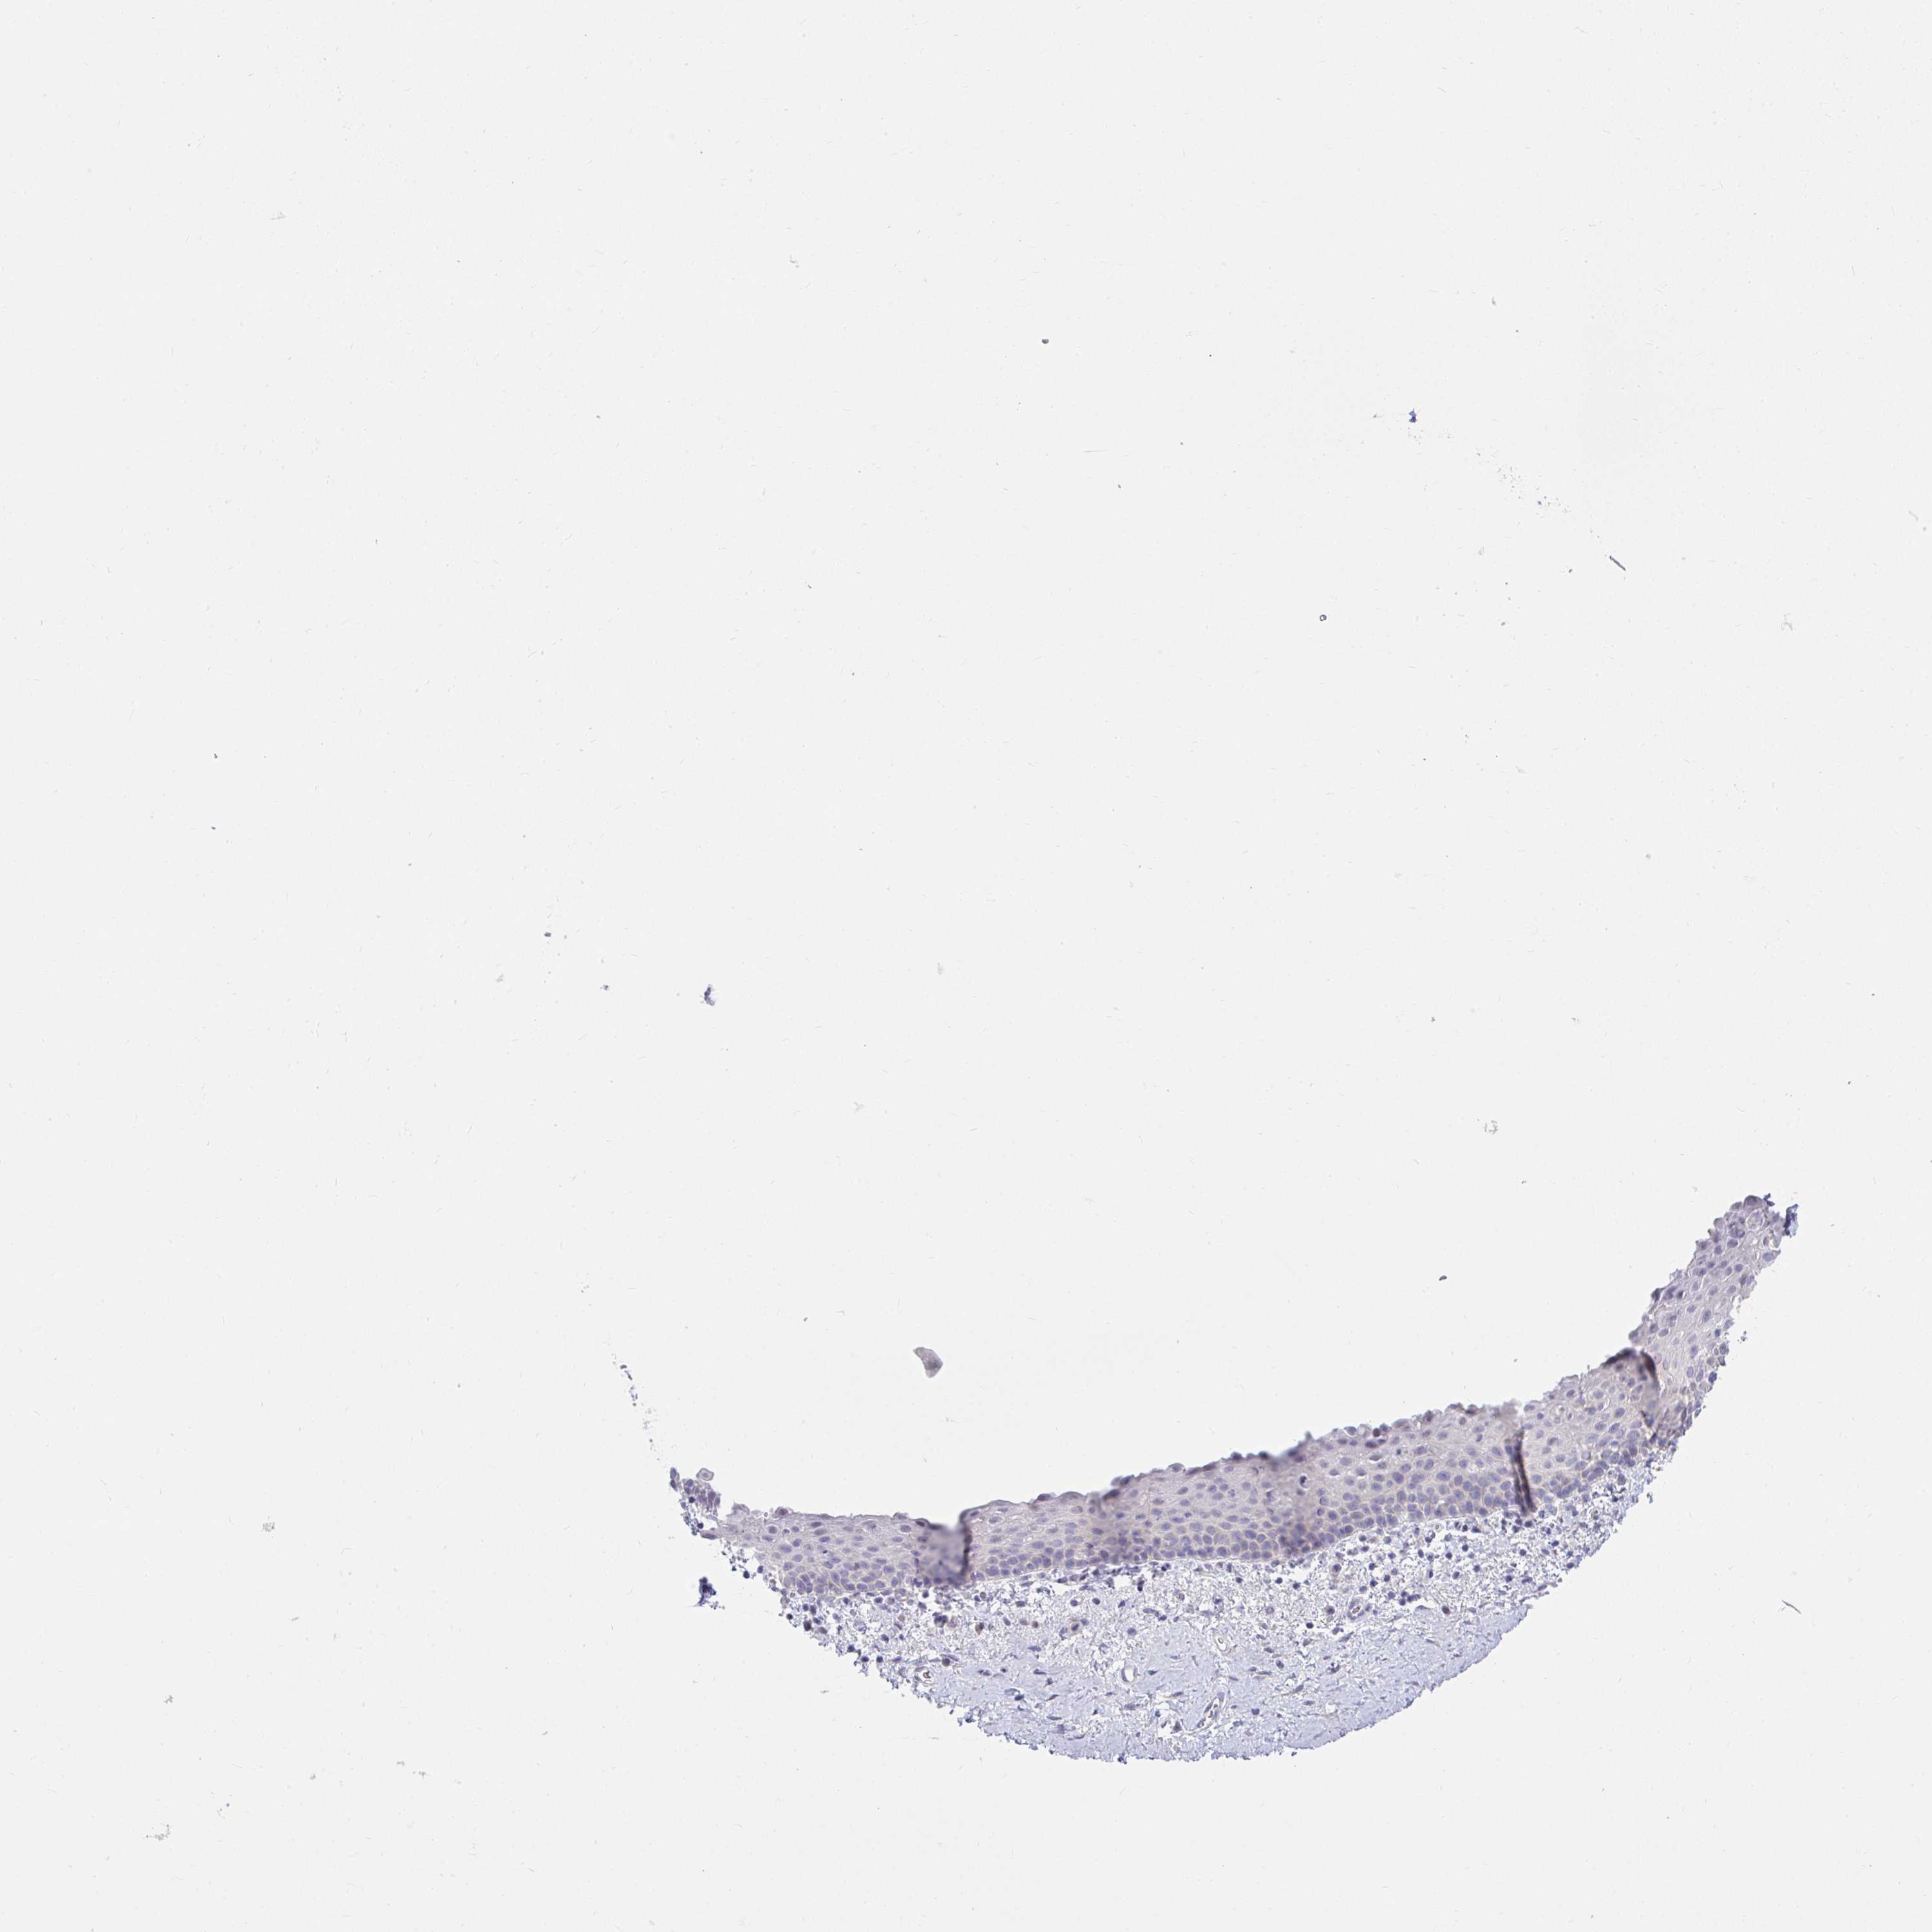

VAGINA - Antibody stainingi

Antibody staining in the annotated cell types in the current human tissue is reported as not detected, low, medium, or high, based on conventional immunohistochemistry profiling in selected tissues. This score is based on the combination of the staining intensity and fraction of stained cells.

Each image is clickable and will lead to virtual microscopy that enables deeper exploration of all samples and also displays staining intensity scores, fraction scores and subcellular localization as well as patient and tissue information for each sample.

Antibody HPA042403

Squamous epithelial cells Not detected